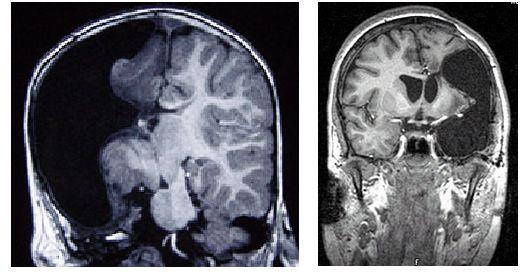

大腦半球切除術(shù)(Hemispherectomy)是一種主要適用于兒童頑固性癲癇的外科手術(shù),涉及全部或部分切除患病的大腦半球或使患病的大腦半球與未患病側(cè)斷開(kāi)連接。

圖 | 大腦半球切除術(shù)(來(lái)源:clevelandclinic.org)

大多數(shù)大腦神經(jīng)網(wǎng)絡(luò)使用兩個(gè)半球來(lái)運(yùn)作。例如,面部識(shí)別涉及大腦皮層的兩側(cè),其它的技能,比如移動(dòng)四肢的能力,則是由大腦的兩邊來(lái)處理的,右半球控制身體左側(cè)的運(yùn)動(dòng),而左半球控制右臂和右腿。